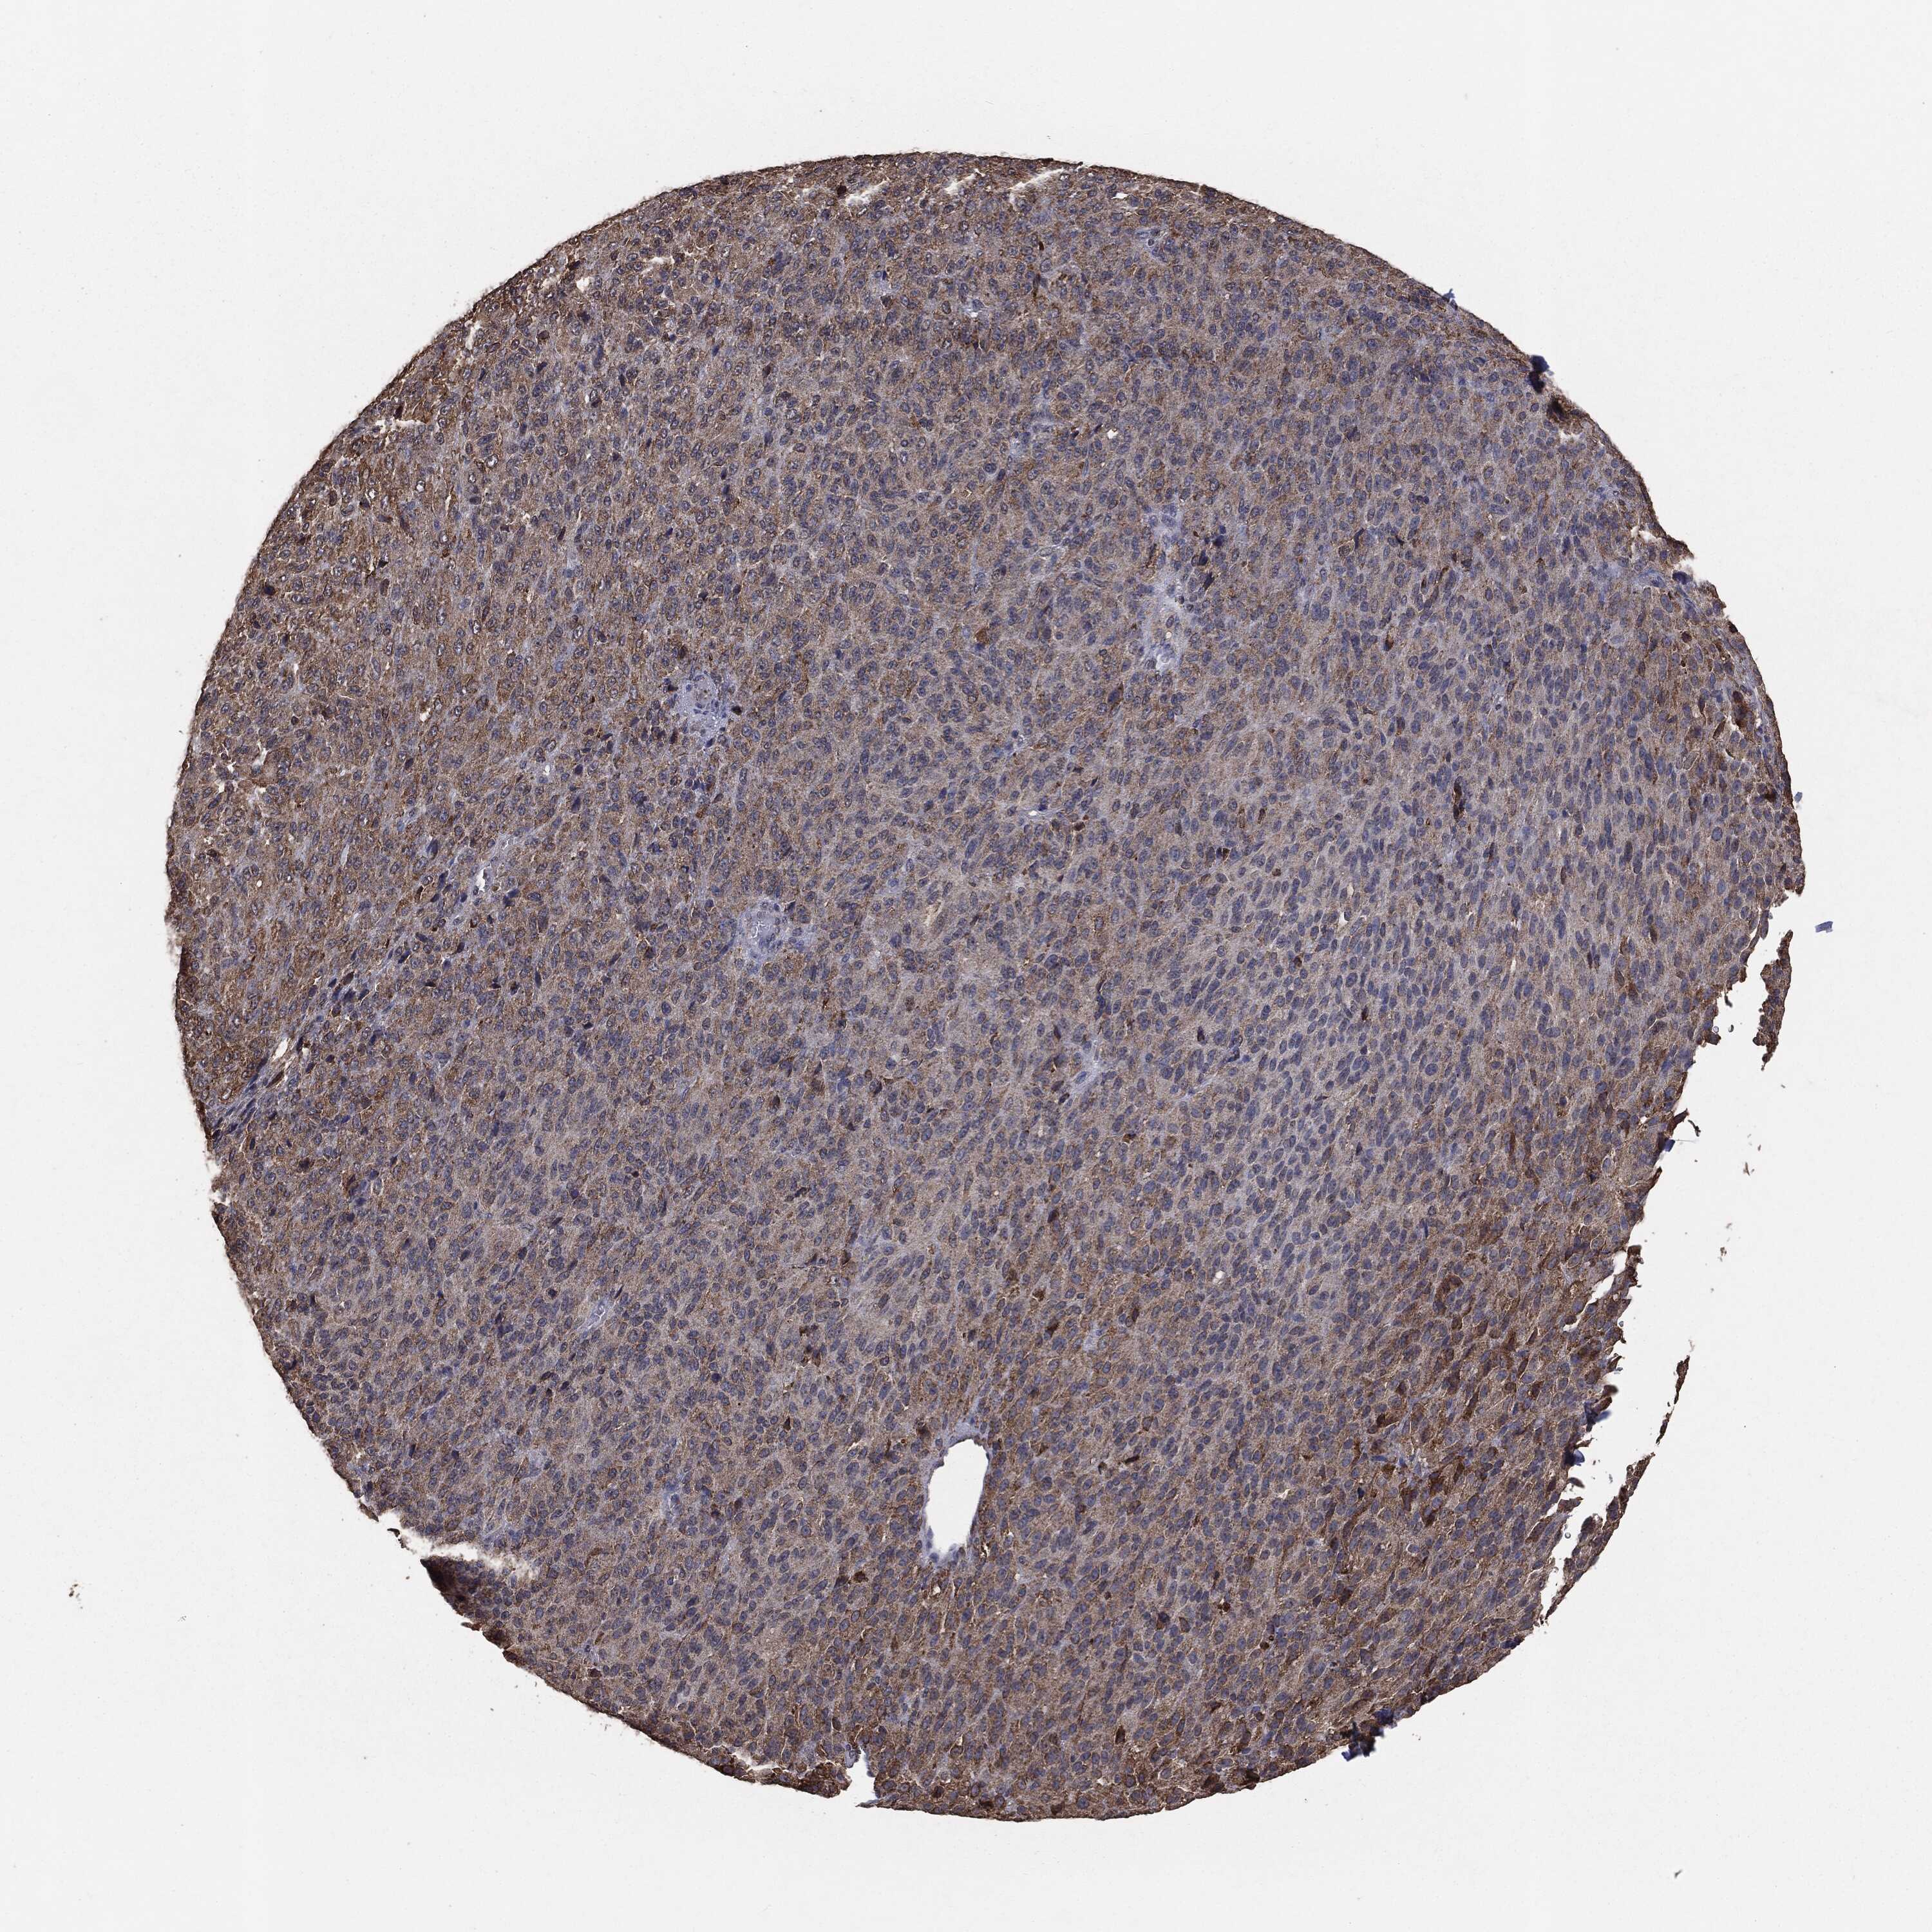

MELANOMA - Protein expressioni

A mouse-over function shows sample information and annotation data. Click on an image to view it in a full screen mode. Samples can be filtered based on level of antibody staining by selecting one or several of the following categories: high, medium, low and not detected. The assay and annotation is described here.

Note that samples used for immunohistochemistry by the Human Protein Atlas do not correspond to samples in the TCGA dataset.

Antibody stainingi

Antibody staining in the annotated cell types in the current human tissue is reported as not detected, low, medium, or high, based on conventional immunohistochemistry profiling in selected tissues. This score is based on the combination of the staining intensity and fraction of stained cells.

Each image is clickable and will lead to virtual microscopy that enables deeper exploration of all samples and also displays staining intensity scores, fraction scores and subcellular localization as well as patient and tissue information for each sample.

CAB069425

CAB080053

CAB080065

CAB080070

CAB080081

CAB080095

CAB080097

Staining

High

Medium

Low

Not detected

Intensity

Strong

Moderate

Weak

Negative

Quantity

>75%

75%-25%

<25%

None

Location

Nuclear

Cytoplasmic/membranous

Cytoplasmic/membranous,nuclear

Malignant melanoma, NOS

Malignant melanoma, Metastatic site